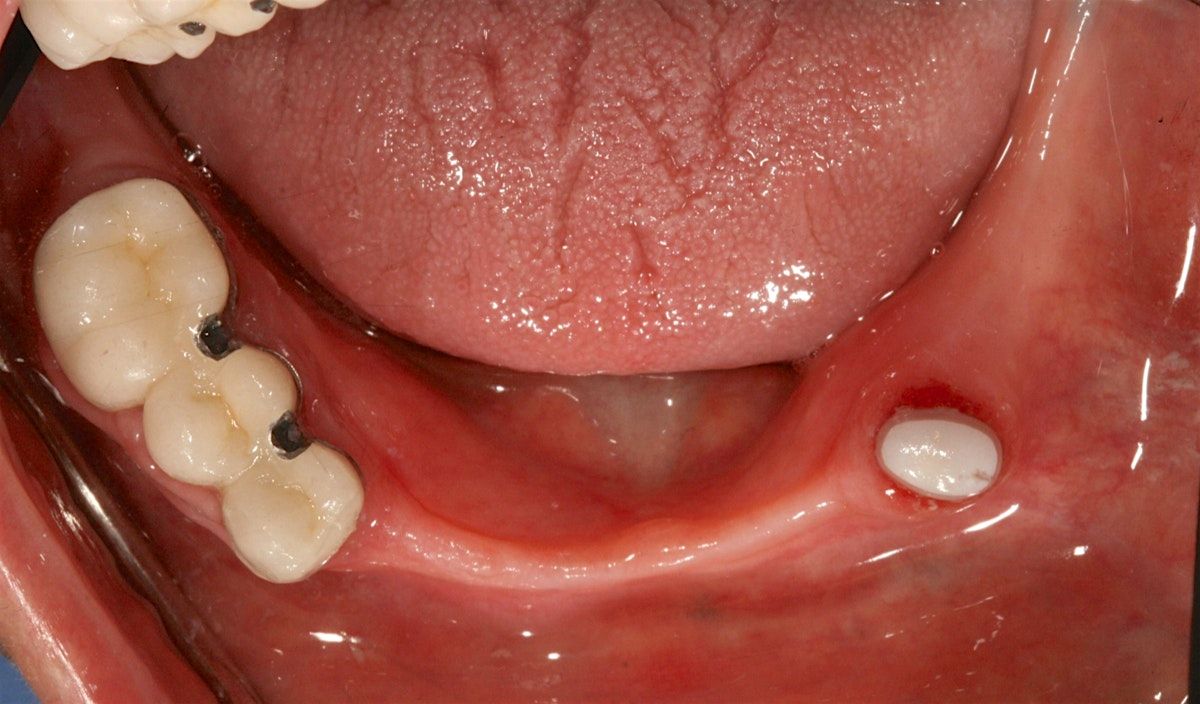

Topics that will be covered include: the principles of RPD design and philosophy, precision partial attachment systems, and implant incorporation into RPD design. 12 CE credits offered through the GDA (also applicable for those attending from out of state).